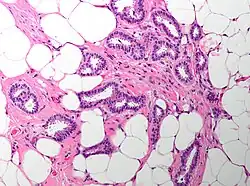

Cribriform carcinoma of the breast showing a cribriform area | |

Invasive cribriform carcinoma of the breast (ICCB), also termed invasive cribriform carcinoma, is a rare type of breast cancer that accounts for 0.3% to 0.6% of all carcinomas (i.e. cancers that develop from epithelial cells) in the breast.[1] It originates in a lactiferous duct as opposed to the lobules that form the alveoli in the breasts' mammary glands (lobules make the milk which the ducts channel to the breast's nipple). ICCB was first described by Dixon and colleagues in 1983 as a tumor that on microscopic histopathological inspection had a cribriform pattern,[2] i.e. a tissue pattern consisting of numerous "Swiss cheese"-like open spaces and/or sieve-like small holes (see adjacent Figure).[3] The latest edition (2019) of the World Health Organization (2019) termed these lesions invasive cribriform carcinomas indicating that by definition they must have a component that invades out of their ducts of origin into adjacent tissues. In situ ductal cancers (i.e. cancers localized entirely within their tissues of origin) that have a cribriform histopathology are regarded as belonging to the group of ductal carcinoma in situ tumors.[4]

The microscopic histopathology of ICCB tumors stained with hematoxylin and eosin shows cribriform areas covering more than 50% of the tumor with the remaining tumor areas showing tubular and/or other histopathological patterns. The cribriform areas consist of small-sized cells with amphophilic (i.e. taking up both the hematoxylin and eosin stains) cytoplasm, indistinct cell boundaries, and small-to-medium sized nuclei that are surrounded by a sharp nuclear membrane and contain finely stippled chromatin (i.e. DNA coated with protein).[17] Numerous open spaces and/or sieve-like small holes lie between these cells (see above photomicrograph) to give the lesions a Swiss cheese-like appearance. The spaces and holes may contain microcalcifications and/or mucins (i.e. high molecular weight, sugar-linked proteins normally produced and secreted by the mammary gland and found in milk).[3] The cells around these spaces and holes sometimes have "apical snouts", i.e. small protrusions on the side of the cells that faces the spaces and holes.[11] Tubular areas (see adjacent photomicrograph of a tubular carcinoma) consist of well-formed tubules lined with mostly normal appearing tubular cells.[17][20] The other histopathological patterns that may occur in these tumor types include the pattern associated with invasive carcinoma of no special type[4] or in uncommon cases the pattern associated with mucinous carcinoma of the breast.[17] The invasive component of these tumors almost always has the cribriform histopathology pattern.[14] All of the tumor cells in ICCB are typically slow-growing as evidenced by their low mitotic index (i.e. the ratio of the number of dividing cells to the total number of tumor cells) or low levels of cellular Ki-67 protein (an index of cell proliferation).[14]